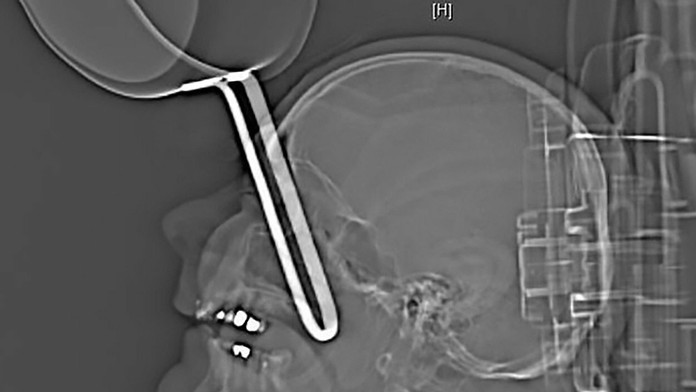

Muž z nemeckého mesta Karlsruhe (64) môže hovoriť o veľkom šťastí v nešťastí. Keď po niekoľkých pohároch alkoholu spadol v kuchyni, pri páde si vrazil rukoväť panvice priamo do lebky.

Nemec mal asi 10-centimetrovú časť panvice priamo v očnici. Poranený muž si stihol zavolať záchranku, ktorá ho v kritickom stave letecky prepravila do nemocnice.

Tam lekári spravili röntgenový snímok a neverili vlastným očiam. Muža museli ihneď operovať. Po niekoľkohodinovom zákroku sa ho podarilo zachrániť. Nemec im môže byť nesmierne vďačný, pretože mu zachránili aj zrak.

Rukoväť panvice mu minula mozog a prešla do lebky pod očnou buľvou. Po siedmich dňoch muža prepustili z nemocnice domov, uviedli noviny.cz.